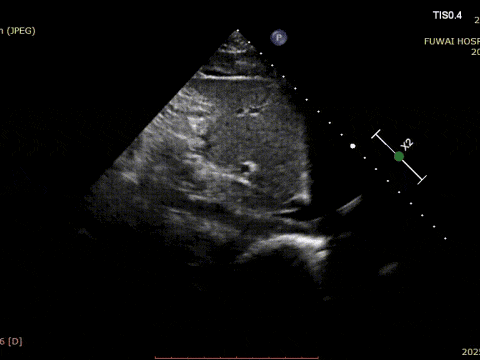

At Fuwai Hospital Shenzhen, Dr. Lu Yaoxing's team recently performed a successful transcatheter closure of a secundum atrial septal defect (ASD) using a MemoSorb biodegradable occluder in a 34-year-old male patient with a rare coronary anomaly.

1. The ASD was central in location, with a measured diameter of approximately 8.1 mm (bicaval view) and 8.2 mm (aortic short-axis view).

2. Coronary CTA revealed an anomalous origin of the left circumflex artery (LCX) from the right coronary sinus, with a course between the aorta and left atrium.

3. The distance between the ASD and the aberrant LCX was only about 6 mm.

4. There was no aortic rim, and the inferior and posterior rims were relatively soft.

Given the proximity of the defect to the coronary artery, a traditional metal occluder posed a risk of compression, especially during physical exertion. A biodegradable ASD occluder (BDASD-I 18 mm) was therefore selected for its flexibility, lower risk of long-term mechanical injury, and ability to degrade into carbon dioxide and water after completing the closure function.

The procedure was guided by TTE following the PAN procedure developed at Fuwai Hospital. This radiation-free, real-time imaging technique offers high-resolution anatomical visualization, ensuring accurate device placement and minimizing complications—particularly valuable in young, reproductive-age patients.